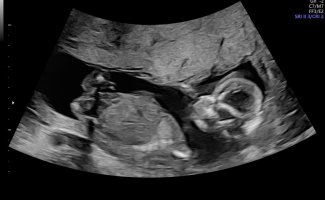

Noen som vil gjette her? 12+5. Usikker på om nub synes på disse bildene?

Jordmor tippet jente. Vi så nub mye tydeligere på skjerm. Ganske lang, rett og en liten vinkel oppover på tuppen. Da lå baby med god bøy på rygg. Andre steder så jeg den sto rett ut.

Senere sa jordmor det kunne se ut som gutt fra andre vinkler.